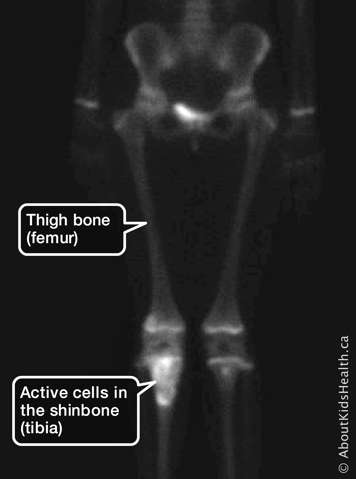

A bone scan is a set of pictures of your skeleton (bones). The scan is usually done to show changes in the bone. A bone scan can find areas in your bone where cells are more active than usual, such as in a tumour. These areas might not show up on a regular X-ray.

In a bone scan, a radiologist will be able to see areas in your bone where there are lots of active cells, which could be a sign of a tumour. They will also be able to see whether cancer from another part of your body has spread (metastasized) to your bones.

A gamma camera will be placed very close to your body. This camera will record the gamma rays the radioactive medicine gives off. Gamma rays are like flashes of light, but our eyes cannot see them. The gamma camera makes an image or movie of your bones in action. Very simply, it will create a living picture of your skeleton. Areas in your bones where the cells are active will look dark in the pictures. Areas where the cells are not active will look lighter.